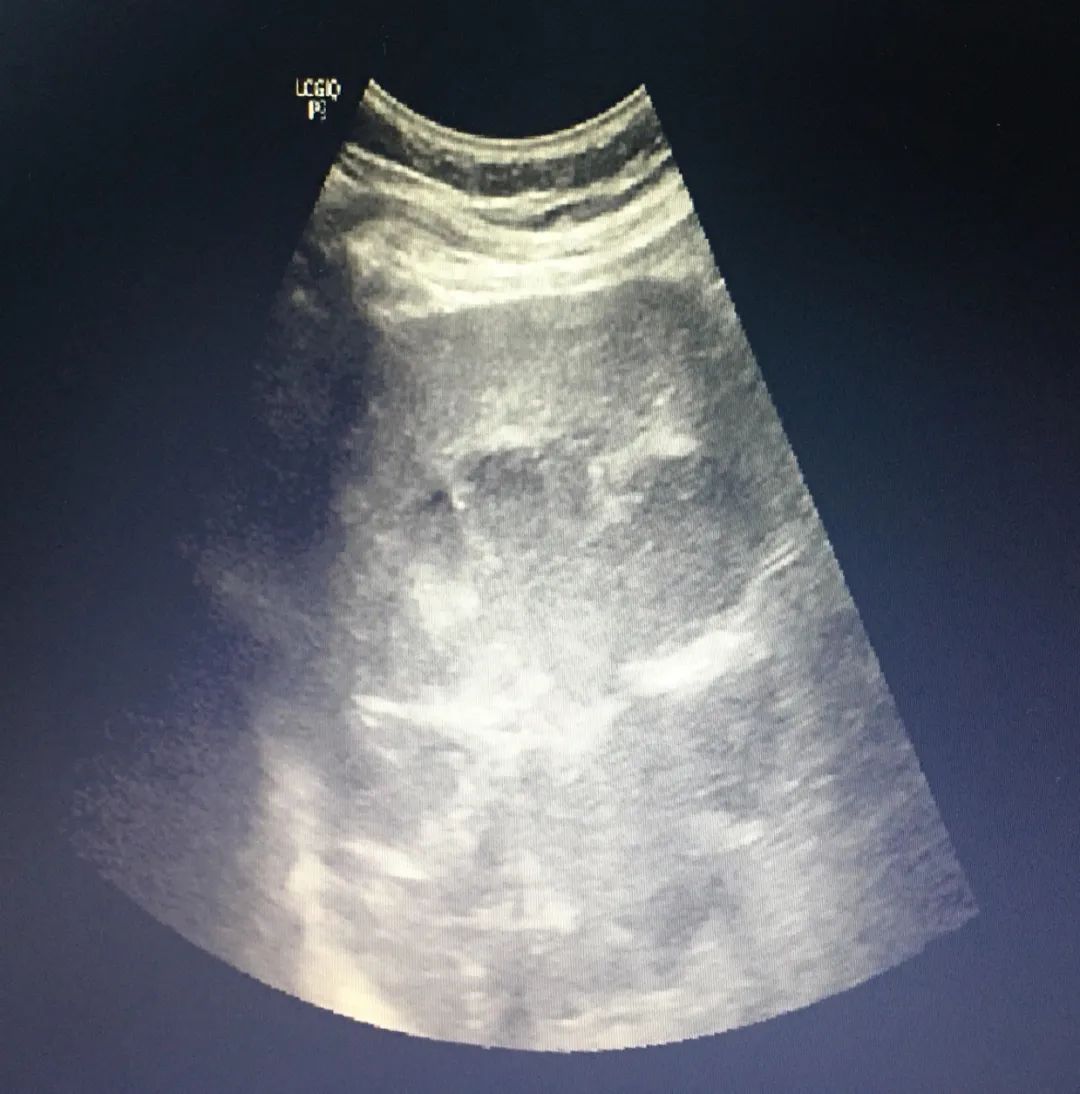

腹部彩超示: 1.肝脾大,肝内低回声,考虑肝囊肿,进一步检查;2.胆囊结石;3.左肾囊肿;

术前彩超示:肝右后叶可探及大小12.2×8.7cm的低回声包块,其内可见分隔光带,术中引流出约100ml浅咖啡色粘稠脓液,术后患者未再有发热,术后3天复查肝功能呈持续好转趋势,CRP、血白细胞等指标明显下降。